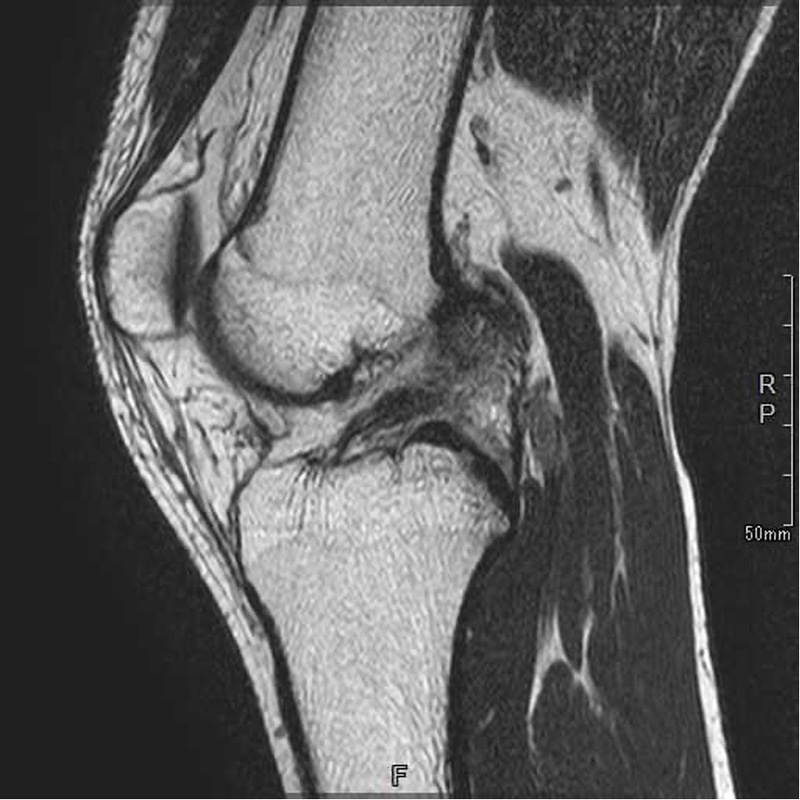

前十字靭帯を損傷するスポーツの場面は大きく分けて2種類あります。ラグビーなどのように相手に膝に直接タックルされることや、バスケットボールなどでジャンプの着地時に相手に直接的に膝に乗られてしまうなど膝に直接外力がかかり前十字靭帯が損傷する接触型の損傷といいます。もう一つの種類はサッカーなどのステップ動作中や体操競技の着地時に膝をねじってしまうことで膝に直接外力がかからない状況で前十字靭帯が損傷する非接触型の損傷です。前十字靭帯が損傷するとレントゲン画像だけではわかりませんが、MRIは大きく変わります。正常な前十字靭帯は黒く太いものがうつっていますが、損傷すると靭帯の連続性がなくなったり、靭帯がはっきりうつらなくなります。